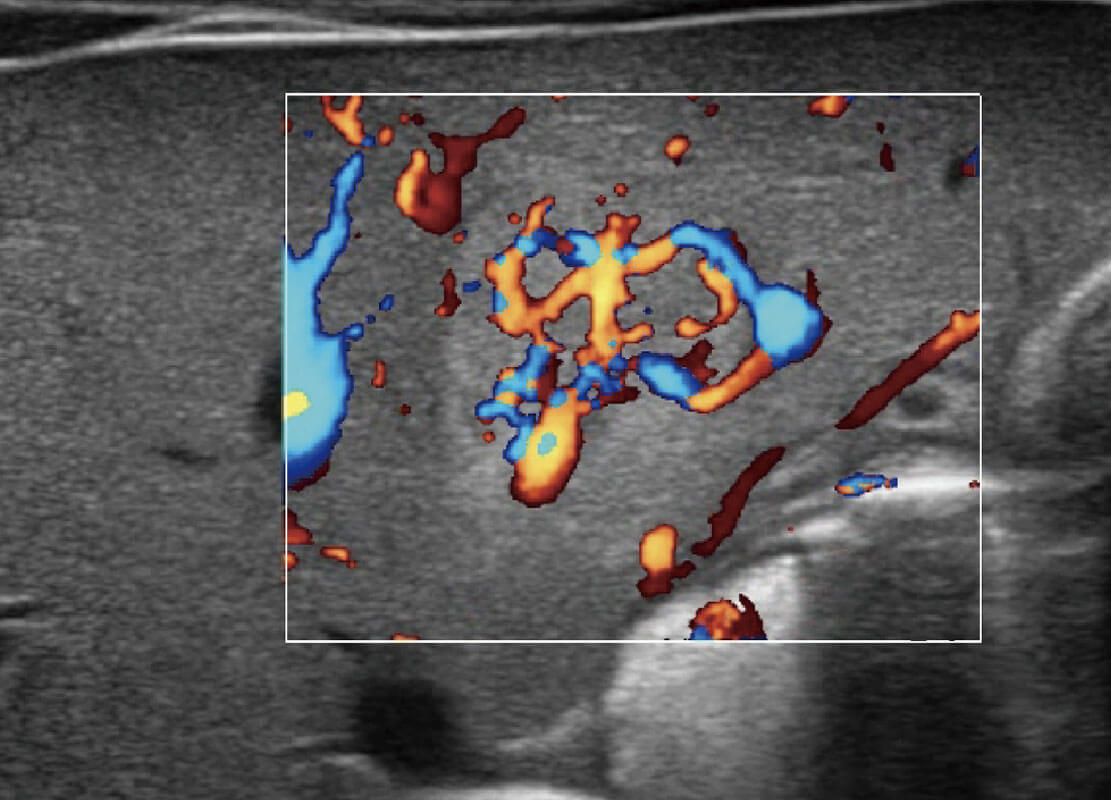

胎儿体循环

P60搭载一系列胎儿心脏成像技术,实现精细的胎儿心脏评估。

四腔心血流